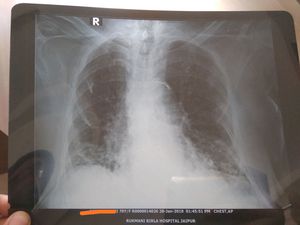

What are the findings in the CXR

Pneumonia